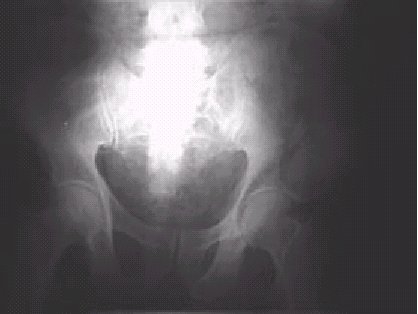

Figura 1.—Radiografía simple AP de pelvis que muestra fractura de ala ilíaca izquierda.